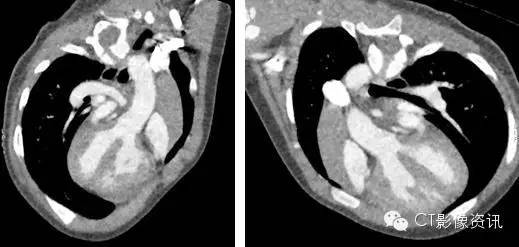

Revolution CT 先心病检查特点及优势

宽(256排*0.625mm, 16 厘米的覆盖宽度) 均匀一致容积增强,Z 轴方向同一心动周期同一时相采集数据,避免运动伪影及错层,有利于减少纤细 PDA肺动脉闭锁等畸形的漏诊。气管重建无错层,成像效果好。

快(转速 280ms) 扫描时间短,曝光采集时间窗更精准,对比剂注射总量减少,保护幼儿肾功能,同时避免了上下腔高密度对比剂伪影,以免干扰肺动脉和肺静脉观察。时间分辨率高,心腔内部结构显示好,检查时减少了因患儿躁动或哭闹造成失败的风险。

低管电压(70kV) 保证了低剂量,同时提高了空间分辨率,提高了碘信号的摄取率,保证低浓度低流率对比剂的使用。(威视派克 270mgI/ml)

低剂量 低管电压再加上智能管电流的应用既保证了影像诊断的可靠性,同时又保证了低剂量,保护了患儿。